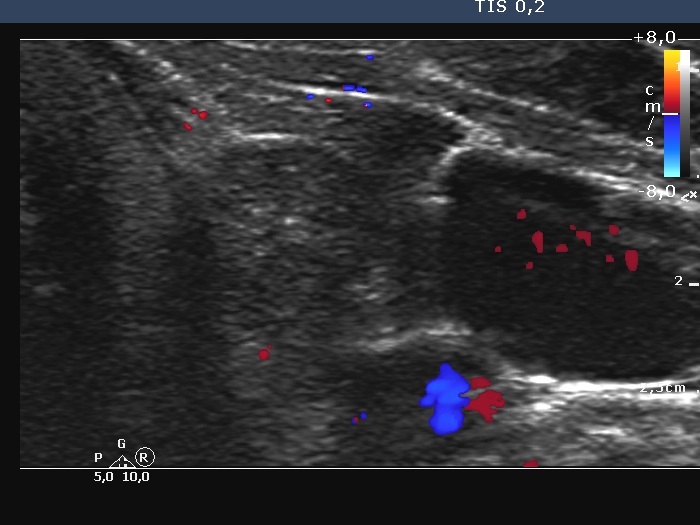

Left lobe, transverse scan, color Doppler mode - enlarged view.